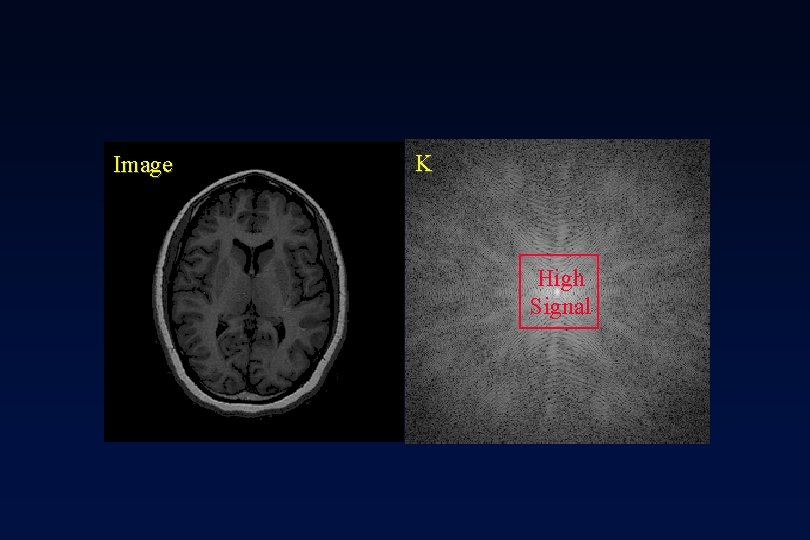

Image K High Signal